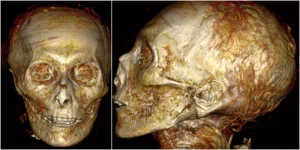

دانشمندان مصری یک مومیایی 3500 ساله را بهصورت دیجیتالی باز کردند و گوشهای از اسرار آن را که قرنها از چشم پژوهشگران دور مانده بود، آشکار ساختند. کارشناسان دانشگاه قاهره از CT اسکن سهبعدی استفاده کردند تا تصویری از آنچه در زیر لایههای لباس و حتی پوست است، ایجاد کنند.

«سحر سلیم» (Sahar Saleem) استاد رادیولوژی و نویسندهی اصلی این مطالعه گفت: «این اسکنها با جزئیات بیسابقهای جسد آمنهوتپ یکم (Amenhotep I) را نشان میدهند.»

چون بقایای آمنهوتپ یکم بسیار عالی درست شده و باقی مانده بود، با حلقههای گل و یک ماسک ظریف با سنگهای رنگارنگ تزئین شده بود، دانشمندان تصمیم گرفتند که این چیدمان را برهم نزنند. اما اکنون به لطف فناوری مقطعنگاری رایانهای (Computer Tomography) یا CT دانشمندان موفق به رمزگشایی از این مومیایی شدند.

آنها با استفاده از اسکنرهای پیشرفته دریافتند که آمنهوتپ اول در زمان مرگ حدود 35 سال سن داشته است. به گفتهی سلیم، قد او حدود 169 سانتیمتر بوده است و ختنه شده، دارای چانهای باریک، بینی باریک و کوچک، موهای مجعد و دندانهای بالایی تقریبا جلوتر بوده است. او همچنین او سالم بهنظر میرسد و هیچ جراحتی دیده نمیشود.

سلیم دربارهی آمنهوتپ یکم گفت: «بهنظر میرسد که او از نظر فیزیکی شبیه پدرش بوده است. معلوم نیست که چرا در این سن کم درگذشته است. ما هیچ زخم یا تغییر شکلی به دلیل بیماری برای توجیه علت مرگ پیدا نکردیم، به جز ضربات متعدد پس از مرگ که احتمالا توسط سارقان قبر و پس از نخستین دفن او صورت گرفته است.»

به گفتهی پژوهشگران این آسیب حدوا 400 سال پس از مرگ آمنهوتپ یکم توسط مسaولان تدفین سلسلهی 21 بهخوبی ترمیم شد. آنها از یک نوار کتان با رزین برای اتصال مجدد سر و گردن به یکدیگر استفاده کردند. محققان همچنین حدود 30 طلسم را در میان بانداژهای آمنهوتپ یکم کشف کردند.